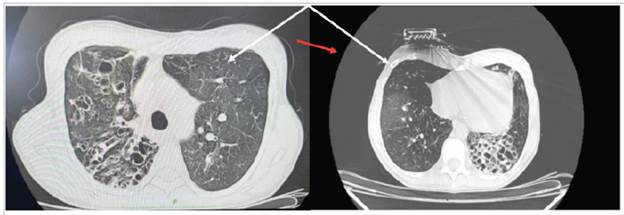

We present the case of a 42-year-old man with a three-month history of colicky abdominal pain in the right iliac fossa with a 6/10 intensity, associated with nausea, episodes of vomiting and a sensation of an intraabdominal mass. At the same time, he reported a 3 kg weight loss, and denied fever or other symptoms associated with the clinical picture. He had a history of rheumatoid arthritis since 2002, initially treated with methotrexate, prednisolone and calcium, and then for a year with etanercept. He had no history of allergies and reported a surgical history of phacoemulsification in 2010 and clavicular osteosynthesis in 2015. On physical exam, he was tachycardic (HR 104 bpm, RR 19 Bpm, T 36.8°C, O2 sat 97%, weight 55 kg, height 160 cm). He had no scleral jaundice, a moist oral mucosa, normal chest expan sion and well-ventilated lungs. The abdomen was soft and painful on palpation of the right iliac fossa, with no signs of peritoneal irritation, and no palpable masses at that time. Blood chemistries were drawn which were within normal ranges (albumin 4.2 gr, negative carcinoembryonic antigen, negative alpha-fetoprotein, creatinine 0.6 mg/dL, complete blood count: leucocytes 8,000, 60% neutrophils, Hgb 11.5 g/dL, Hct 34.5%, platelets 180,000, BUN 20 mg/dL). An abdominal ultrasound reported concentric wall thickening of the ileocecal valve; a subsequent colonoscopy showed a tumor-like lesion in the ascending colon, with the etiology to be determined by biopsy (Figure 1, A, B). Following this, the hematoxylin and eosin-stained pathology showed granulomas in the colonic mucosa, and special Ziehl Neelsen staining showed Mycobacterium tuberculosis granulomas, with a final diagnosis of active chronic granulomatous ul cerative colitis due to Mycobacterium tuberculosis (Figure 2: A, B, C).